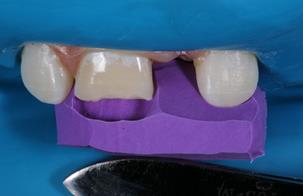

In the following session, direct restoration of the upper right central incisor was performed with MCR (Vittra APS Unique) (FGM Dental Group, Joinville-SC, Brazil). In this occasion, considering the extent of the fracture, a silicone matrix (Perfil, Coltene, Rio de Janeiro-RJ, Brazil) was used to restore the palatal face. The restorative clinical sequence covered: 1) Infiltrative anesthesia, with 2% mepivacaine (adrenaline vasoconstrictor 1:100,000), to remove the GIC, with a #2 Jet carbide drill (Labordental, São Paulo-SP, Brazil), mounted at low speed handpiece; 2) Finishing the enamel in the cavo-surface angle, with diamond tip #1190F (Kavo, Joinville-SC, Brazil); 3) Prophylaxis of the anterior superior teeth with pumice paste and water, with the aid of a Robson brush (Ultra-soft, American Burrs, Palhoça-SC, Brazil); 4) Modified rubber dam isolation; 5) Acid etching of enamel and dentin with 37% phosphoric acid (Biodinâmica, Ibiporã- PR, Brazil), for 30 seconds on enamel and 15 seconds on dentin; 6) Rinsing with a water jet to remove the conditioning agent, for 30 seconds; 7) Drying the operative field with an air jet and the conditioned dentin, with a paper filter (Melitta, São Paulo-SP, Brazil); 8) Application of two layers of the adhesive system (AS) (Adper Single Bond 2, 3M ESPE, Sumaré-SP, Brazil), with the aid of a micro-applicator brush (Cavibrush regular, FGM, Joinville-SC, Brazil), actively, for 15 seconds; 9) Removal of excess AS with the aid of a clean micro-applicator brush and time interval for solvent evaporation; 10) Light cure of the AS with a Radii-Call- SDI device (Southern Dental Industries, São Paulo- SP, Brazil), with an irradiance of 1200 mW/cm2, for 20 seconds; 11) Positioning of the silicone matrix (Figure 3) to restore the palatal face, based on the insertion of the MCR Vittra APS Unique (FGM Dental Group, Joinville-SC, Brazil), and light cure with the LED-based device; 12) Using the incremental technique, with the aid of an insertion spatula and brush, the area corresponding to the dentin was restored with MCR Vittra APS Unique (FGM Dental Group, Joinville-SC, Brazil) with characterization of the volume and anatomy (grooves development) of this substrate (Figure 4). MCR was also inserted over the cavo-surface angle to mask the

transition line between the tooth and the restored area until the entire buccal surface was completed. All CR increments were light-cured for 40 seconds; 13) Immediate finishing of the proximal surface with a #12 scalpel blade (Feather Safety Razor, Osaka, Japan), on the palatal surface with multi-bladed drill #9406 (Microdont, São Paulo-SP, Brazil) and on the buccal surface with sanding discs (Diamond Master, FGM Produtos Odontológicas, Joinville-SC, Brazil) (Figure 5).

Figure 4 Clinical condition after restoration of the area corresponding to dentin and characterization of the development grooves.